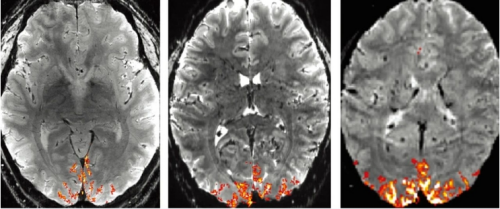

研究人员实现了一系列技术改进,极大地提高了功能性磁共振成像仪器(fMRI)的空间分辨率。得益于这种技术进展,fMRI成像体素(3D像素)的每边长不到0.5毫米。这些精细粒度的体素突破了人脑结构的一个相对重要的阈值,可大致达到神经元功能簇的级别。

研究人员将这种成像仪称为NexGen 7T,其配有一个7特斯拉磁体,分辨率比以前的7T fMRI机器提高了10倍。研究人员表示,扫描仪的精细级别可以解释很多情况,例如,一些大脑区域的广泛功能性组织和其他区域不同层神经元活动的情况。

NexGen 7T fMR(左)内有一个7特斯拉超导电磁铁。该机器的分辨率高于标准的3T医院扫描仪右)和传统7T成像仪(中)

其总体效果是空间分辨率达到了广泛使用的fMRI仪器的50多倍,超过其他7T fMRI一个数量级。在某些情况下,体素从约1微升(1立方毫米)缩小到不到0.1微升,相当于较粗的沙子大小。

荷兰斯宾诺莎神经成像中心主任塞尔日•迪穆兰(Serge Dumoulin)表示,该扫描仪能够提供更高分辨率的功能性大脑图像,包括大脑皮层在内的大脑上部区域。该设备还可以帮助揭示大脑其他区域的详细结构,如脑干和小脑,他说,这些区域“通常超出了传统神经成像的视野”。